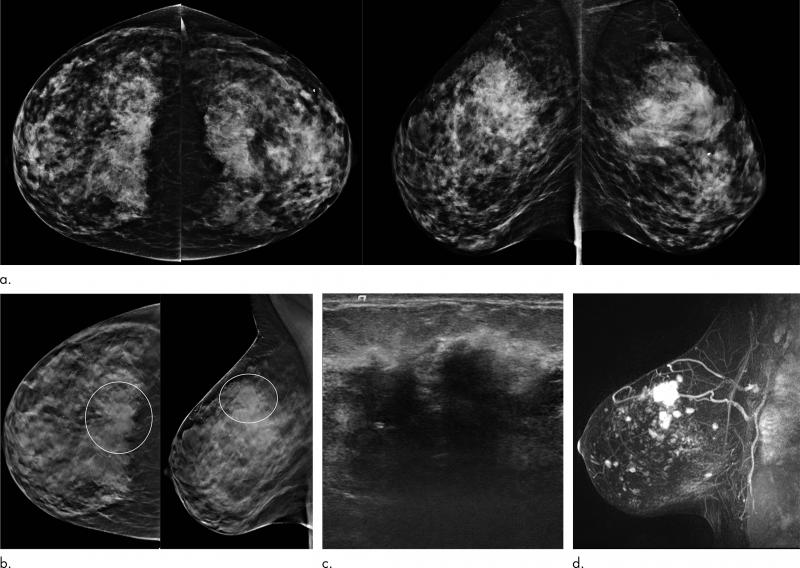

Images in a 57-year-old woman noted to have "good prognosis" invasive cancer detected at digital breast tomosynthesis (DBT) screening. (a) Craniocaudal view of the left breast obtained with the two-dimensional digital mammography (DM) portion of the DM/DBT screening study demonstrates a subtle area of distortion in the medial left breast. (b) Single-slice image from the left craniocaudal DBT portion of the screening study shows an area of bridging distortion (circle). (c) Electronically enlarged image of the area of concern seen on the left craniocaudal view in a single DBT slice as shown in b. (d) Targeted US scan demonstrates two small adjacent irregular solid masses. US-guided core biopsy yielded an invasive carcinoma of the tubular subtype that was estrogen receptor positive, progesterone receptor positive, and human epidermal growth factor receptor 2 negative. The results of the sentinel node biopsy were negative. Image courtesy of the Radiological Society of North America